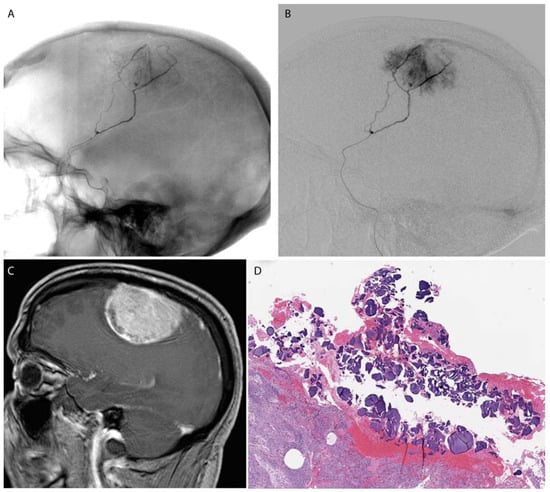

Figure 3.

A falcine meningioma was pre-operatively embolized using PVA microspheres. A microcatheter (A,B) was advanced to a branch of the middle meningeal artery supplying the tumor (C). Post-surgical histology shows PVA microspheres within the tumoral tissue (D).